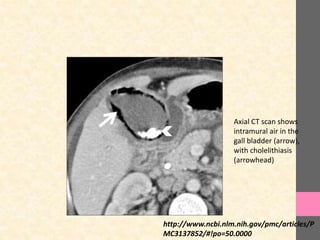

Axial CT scan shows

intramural air in the

gall bladder (arrow),

with cholelithiasis

(arrowhead)

Axial CT scanshows intramural air in the gall bladder (arrow), with cholelithiasis (arrowhead) http://www.ncbi.nlm.nih.gov/pmc/articles/P MC3137852/#!po=50.0000